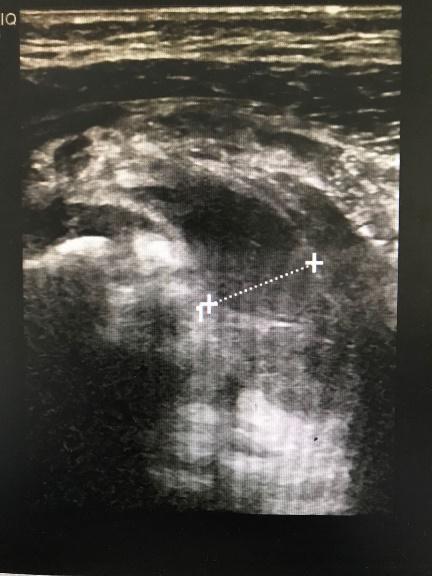

| 图 4 出现髋脱位 |

病理性髋关节脱位发生率高,达81.8%(9/11)。其中6例(54.6%)患儿入院时已有病理性髋关节脱位或半脱位情况,1例为高位脱位;3例患儿治疗过程中出现病理性髋关节脱位或半脱位。5例病髋患儿经一次手术脓肿切排冲洗引流、抗感染及人类位支具固定治疗后髋关节复位(脓肿切排时予检查髋关节复位及稳定情况从而判断是否使用支具);1例行手术切开复位后石膏固定维持复位;1例MRSA感染患儿经4次手术脓肿切排冲洗引流及支具治疗后髋关节复位;1例MSSA感染患儿入院时已有高位脱位,经清创冲洗引流后感染控制,但仍遗留高位脱位情况,以后需要进一步行重建手术治疗;1例目前有残存髋关节半脱位。36.4%放射学预后满意,63.6%(7/11)放射学预后不满意,18.2%(2/11)有残留畸形需要行重建手术。11例患儿的一般情况见表 1。病理性髋关节脱位后支具治疗见图 5。

| 图 5 治疗过程中出现髋脱位,人类位支具固定,提示复位 |